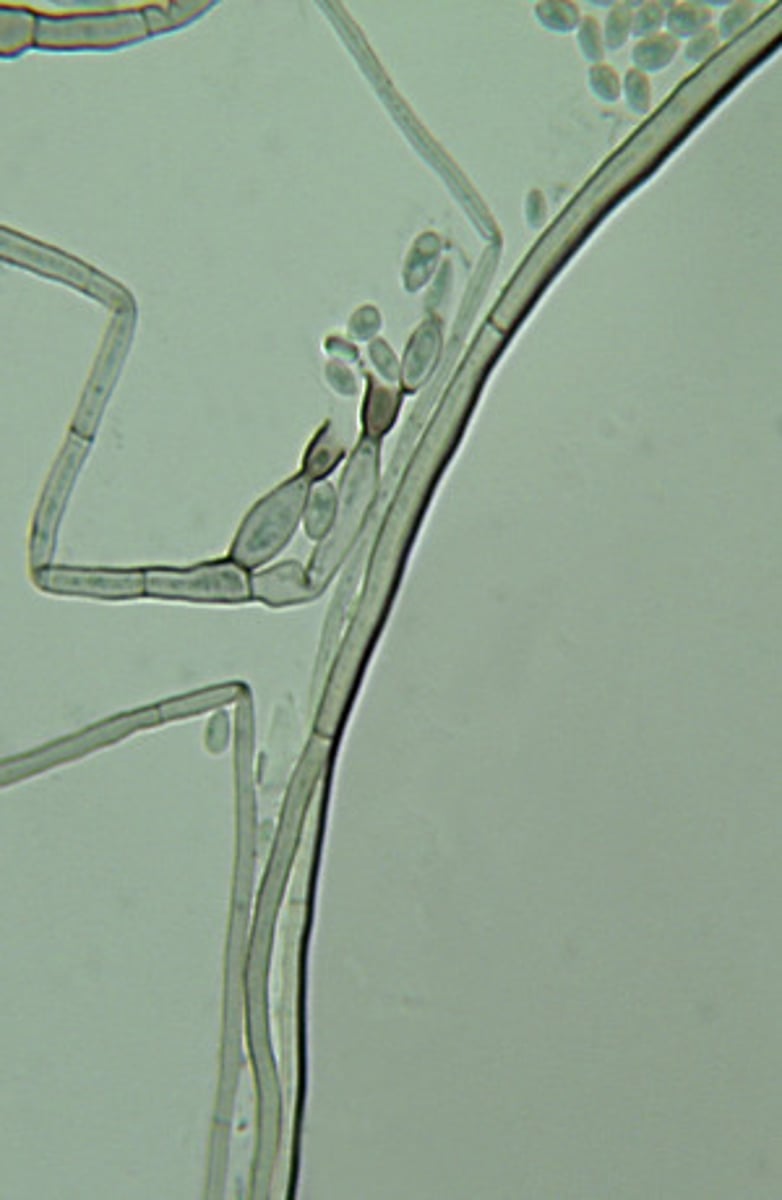

This result of a hair perforation test is typical for which of the following fungi?

Trichophyton mentagrophytes

Trichophyton mentagrophytes produces hyphal structures that invade hair shafts forming cone-shaped perforations. This is a useful test to differentiate dermatophytes.